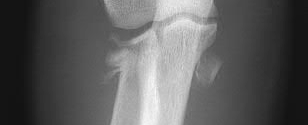

A 25-year-old female is involved in a motor vehicle collision. She presents with the isolated injury seen in Figures A through D. Her leg is swollen but her skin is intact. She has no clinical signs of compartment syndrome. Which of the following treatment options will allow for maintenance of fracture alignment and minimize the risk of soft tissue complications?

The patient presents with a closed distal third metaphyseal-diaphyseal distal tibia fracture with simple intra-articular extension. Immediate intramedullary nailing along with percutaneous fixation of the articular component provides appropriate restoration of length, rotation and alignment and minimizes the risk of wound complication.

Displaced distal third tibia fractures may be associated with simple intraarticular extension. Operative treatment of intra-articular distal tibia fractures has historically been performed with open reduction and internal fixation. Early open reduction and plate fixation of pilon fractures has been associated with high rates of infection and wound complication. In select patterns with simple articular extension, percutaneous screw fixation and medullary nailing may provide appropriate reduction with minimal soft-tissue risk.

Figures A and B demonstrate a distal third tibial shaft fracture with simple intra-articular extension. The axial and coronal CT cuts in Figures C and D further clarify the articular injury. Illustrations A and B demonstrate a comminuted distal third tibial fracture with simple intra-articular extension. Illustrations C and D are fluoroscopic images of the same injury after intramedullary nailing and percutaneous fixation of the articular component.